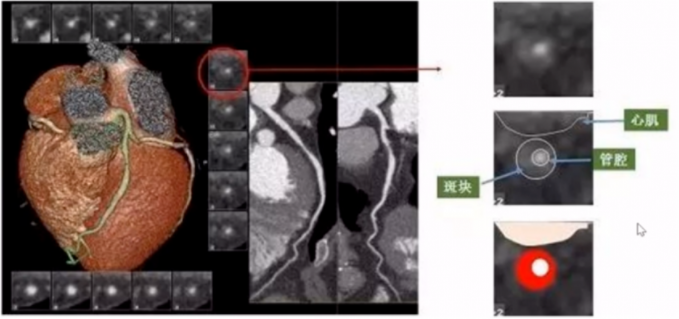

3、冠脉探针

评价狭窄程度。是以表面成像中的小点为中心,向上向下1mm为1层,分别显示数个断层,观察一定长度冠脉管腔横截面。

图15

仔细观察存在病变的探针,中间白色为管腔,白色管腔周围灰色的组织为非钙化斑块,该斑块呈环形生长。